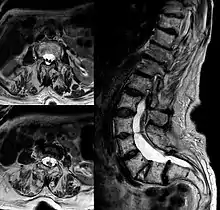

Adult presentation in diastematomyelia is unusual. With modern imaging techniques, various types of spinal dysraphism are being diagnosed in adults with increasing frequency. The commonest location of the lesion is at first to third lumbar vertebrae. Lumbosacral adult diastematomyelia is even rarer. Bony malformations and dysplasias are generally recognized on plain x-rays. MRI scanning is often the first choice of screening and diagnosis. MRI generally give adequate analysis of the spinal cord deformities although it has some limitations in giving detailed bone anatomy. Combined myelographic and post-myelographic CT scan is the most effective diagnostic tool in demonstrating the detailed bone, intradural and extradural pathological anatomy of the affected and adjacent spinal canal levels and of the bony spur.